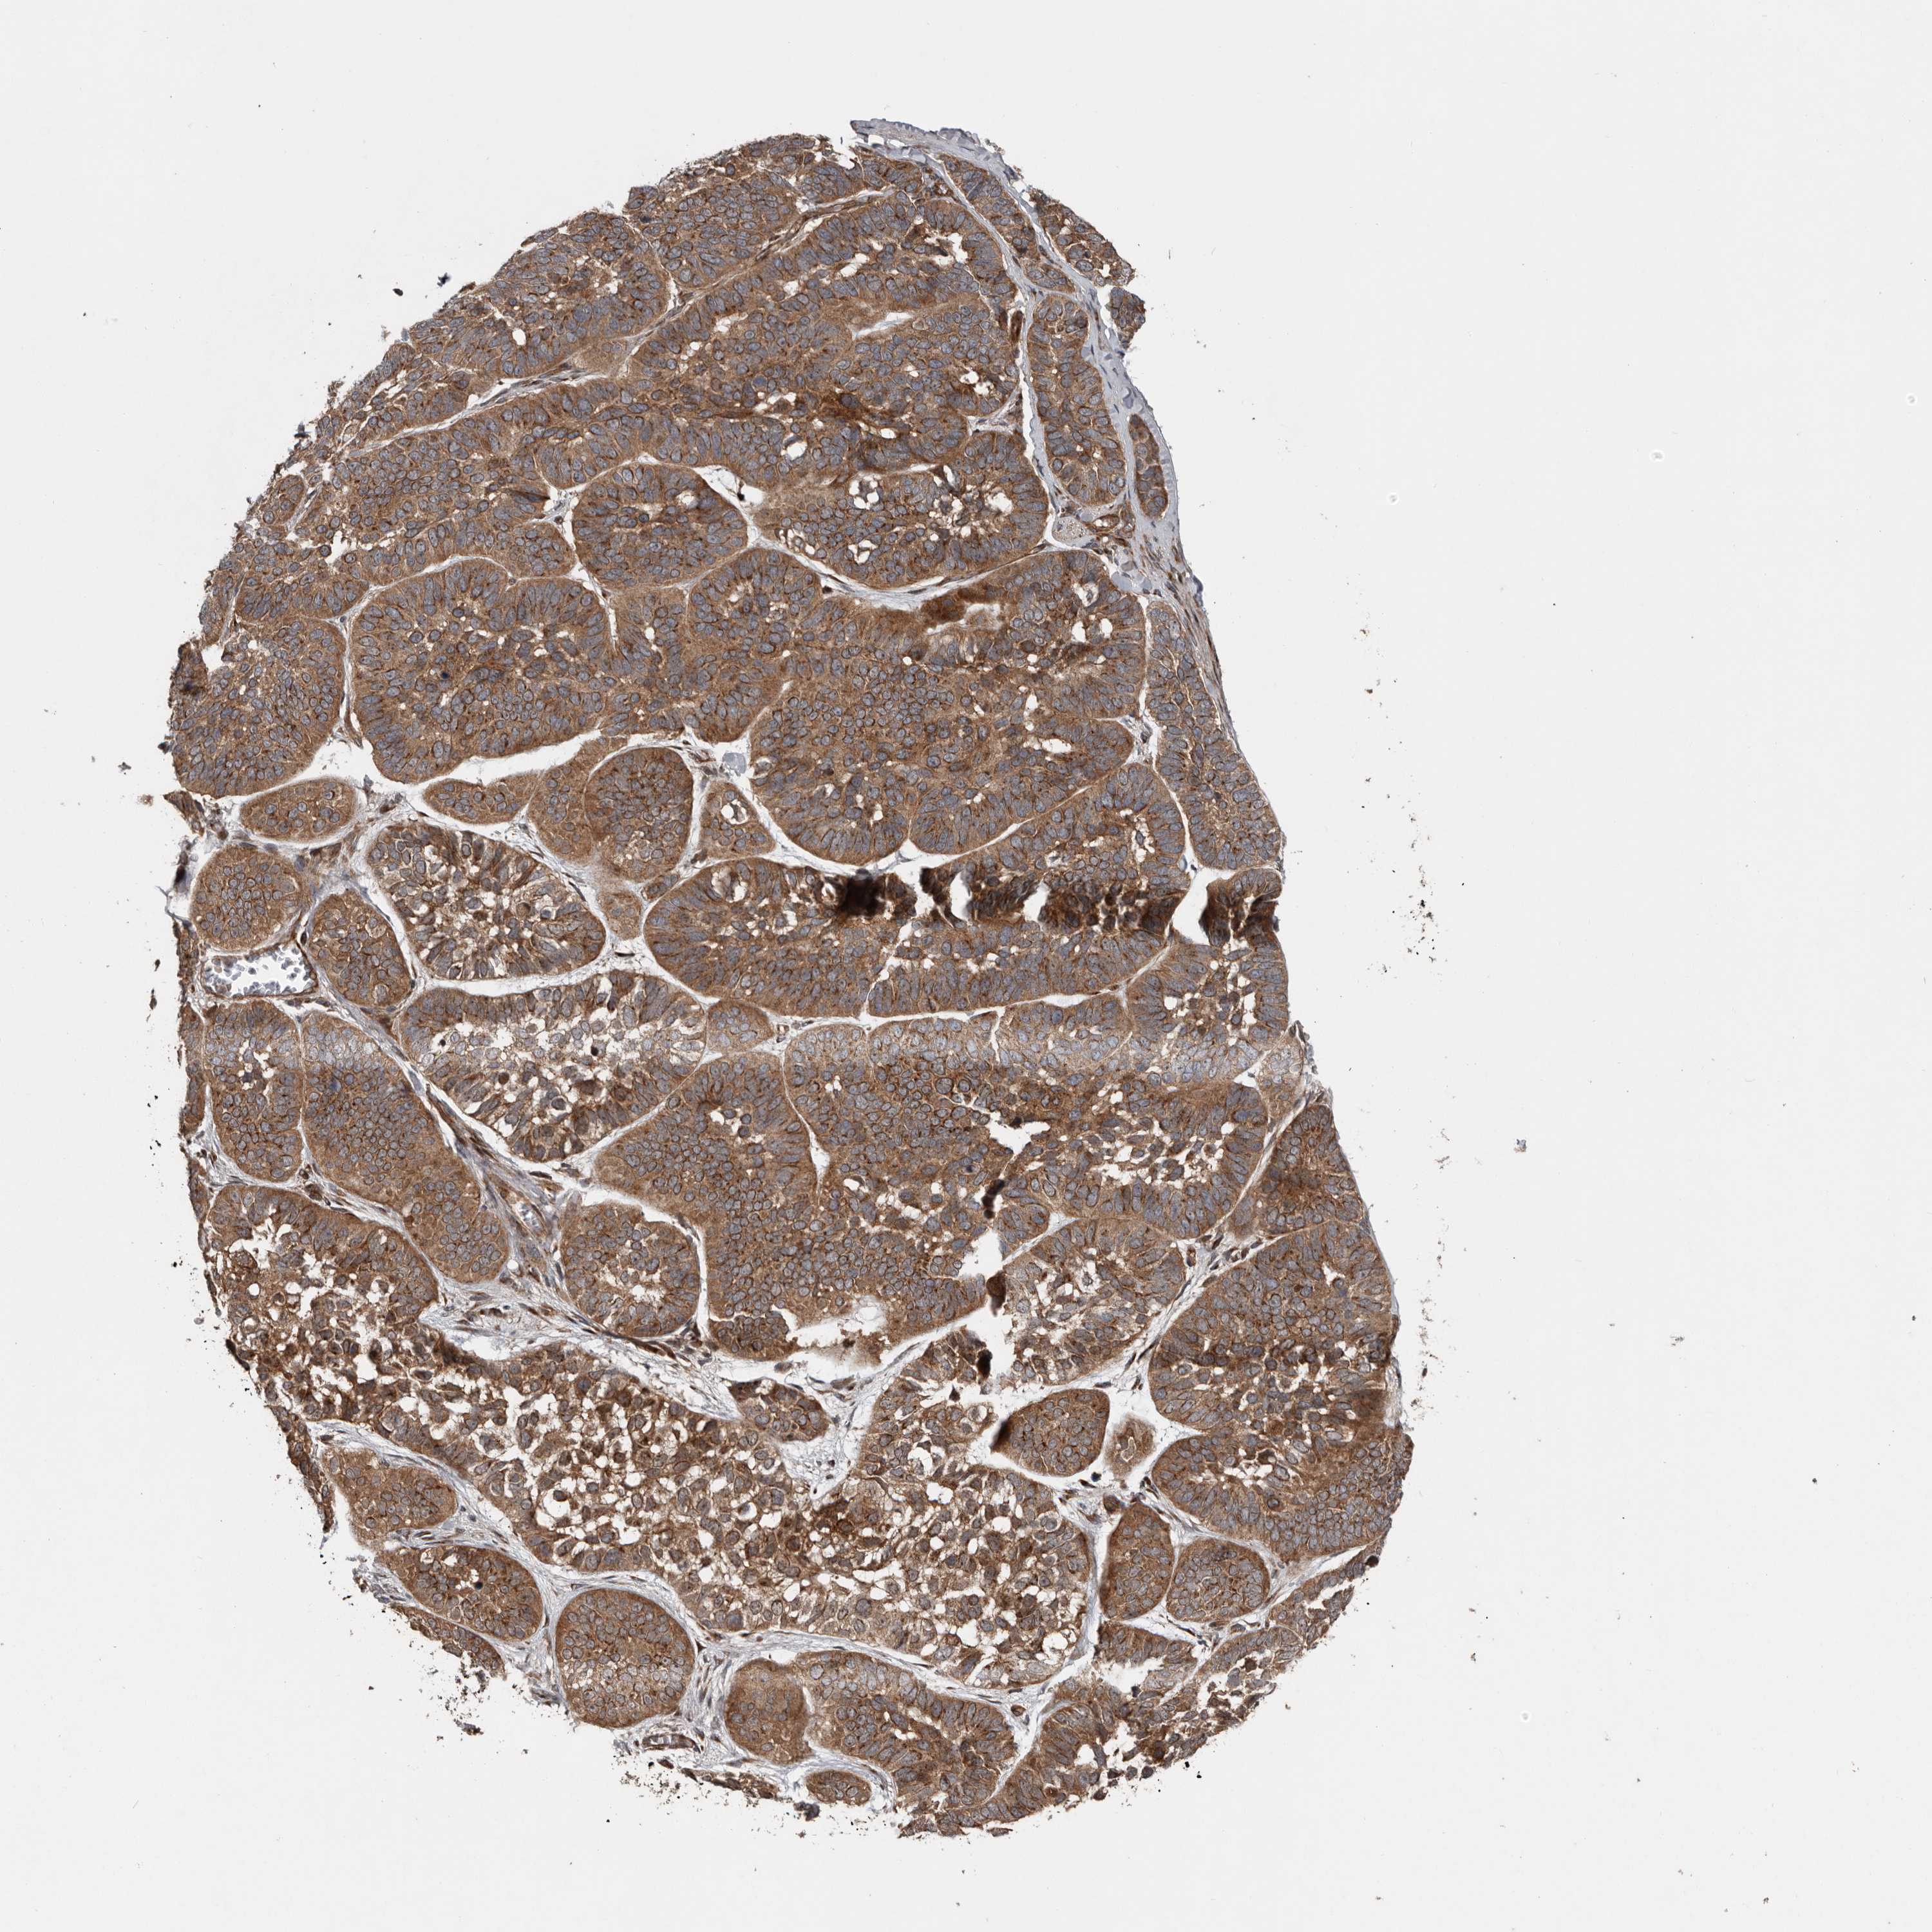

SKIN CANCER - Protein expressioni

A mouse-over function shows sample information and annotation data. Click on an image to view it in a full screen mode. Samples can be filtered based on level of antibody staining by selecting one or several of the following categories: high, medium, low and not detected. The assay and annotation is described here.

Each image is clickable and will lead to virtual microscopy that enables deeper exploration of all samples and also displays staining intensity scores, fraction scores and subcellular localization as well as patient and tissue information for each sample.

Squamous cell carcinoma, NOS